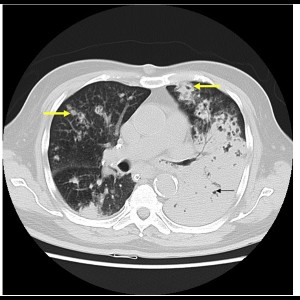

CT in detection and diagnosis of thoracic conditions in symptomatic HIV patients

CT in detection and diagnosis of thoracic conditions in symptomatic HIV patients

READ MORE

CT in detection and diagnosis of thoracic conditions in symptomatic HIV patients

CT in detection and diagnosis of thoracic conditions in symptomatic HIV patients

READ MORE

Pulmonary nocardiosis: Under-diagnosed respiratory opportunistic infection

Pulmonary nocardiosis: Under-diagnosed respiratory opportunistic infection - A Case report

READ MORE

Pulmonary nocardiosis: Under-diagnosed respiratory opportunistic infection

Pulmonary nocardiosis: Under-diagnosed respiratory opportunistic infection - A Case report

READ MORE